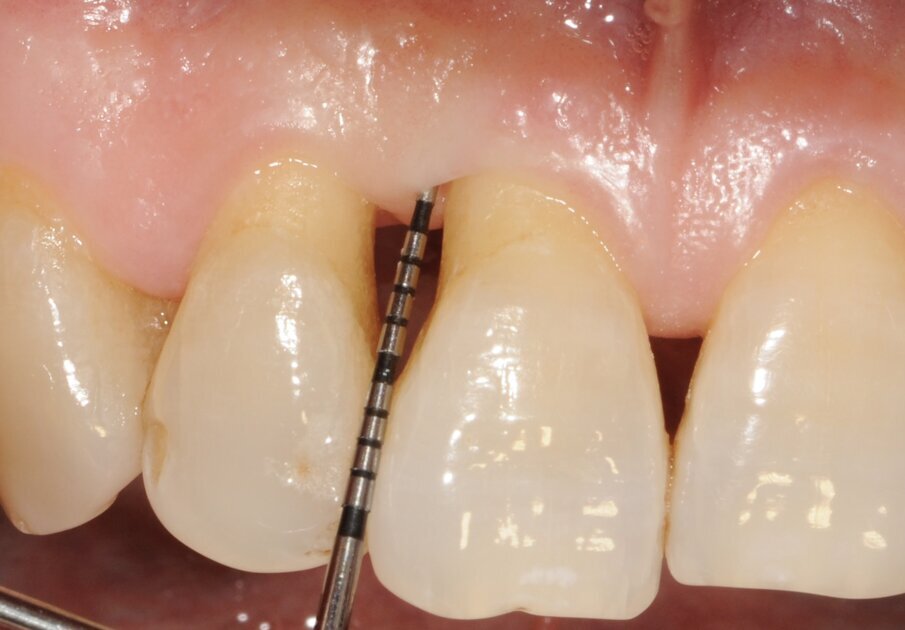

Un paziente di 56 anni non fumatore viene riferito alla nostra osservazione per il trattamento della parodontite. Dopo aver effettuato la diagnosi (parodontite generalizzata Stadio III, Grado C) il paziente è sottoposto a due sedute di scaling sopra gengivale (step 1) e successivamente a 4 sedute di debridement sotto gengivale effettuato con strumenti ultrasonici e manuali (step 2). Al momento della rivalutazione si registra un miglioramento degli indici di placca e di sanguinamento (FMPS e FMBS ≤ 20%) e una riduzione di tutte le tasche parodontali (PD<4 mm) in ciascun sestante a eccezione del secondo sestante. In questa regione si registra una tasca residua con PD = 6 mm a carico dell’elemento 1.1, associata a un riassorbimento osseo radiografico prevalentemente orizzontale (Figg. 1, 2). Considerando il miglioramento di tutti i parametri e degli indici parodontali e la presenza di una tasca con PD = 6 mm a carico di un solo elemento dentario si decide di ritrattare l’elemento 1.1 con terapia non chirurgica (step 3). La nuova ristrumentazione è stata effettuata seguendo il protocollo Clean&Seal che prevede l’associazione di ipoclorito di sodio stabilizzato con amminoacidi e acido ialuronico reticolato ad alto peso molecolare in combinazione con il debridement sotto gengivale. Dopo anestesia locale, è stato applicato all’interno della tasca l’ipoclorito di sodio stabilizzato con amminoacidi e lasciato agire per circa 60 secondi (Fig. 3). Successivamente è stata effettuata la strumentazione sotto gengivale mediante l’utilizzo di strumenti ultrasonici e manuali (Figg. 4, 5). Alla fine della procedura di strumentazione, nella tasca è stata effettuata un’irrigazione con soluzione salina sterile e la procedura di applicazione di ipoclorito di sodio e di strumentazione meccanica è stata ripetuta per 4 volte. Un fattore critico per garantire un risultato migliore è di evitare di instillare qualsiasi soluzione a base di clorexidina nella tasca, in quanto inibisce l’adesione cellulare. Alla fine del trattamento meccanico è stato inserito l’acido ialuronico reticolato ad alto peso molecolare all’interno della tasca per stabilizzare il coagulo e accelerare la guarigione (Fig. 6). Il controllo clinico è stato effettuato dopo 6 settimane dal trattamento con completa chiusura della tasca (Fig. 7).